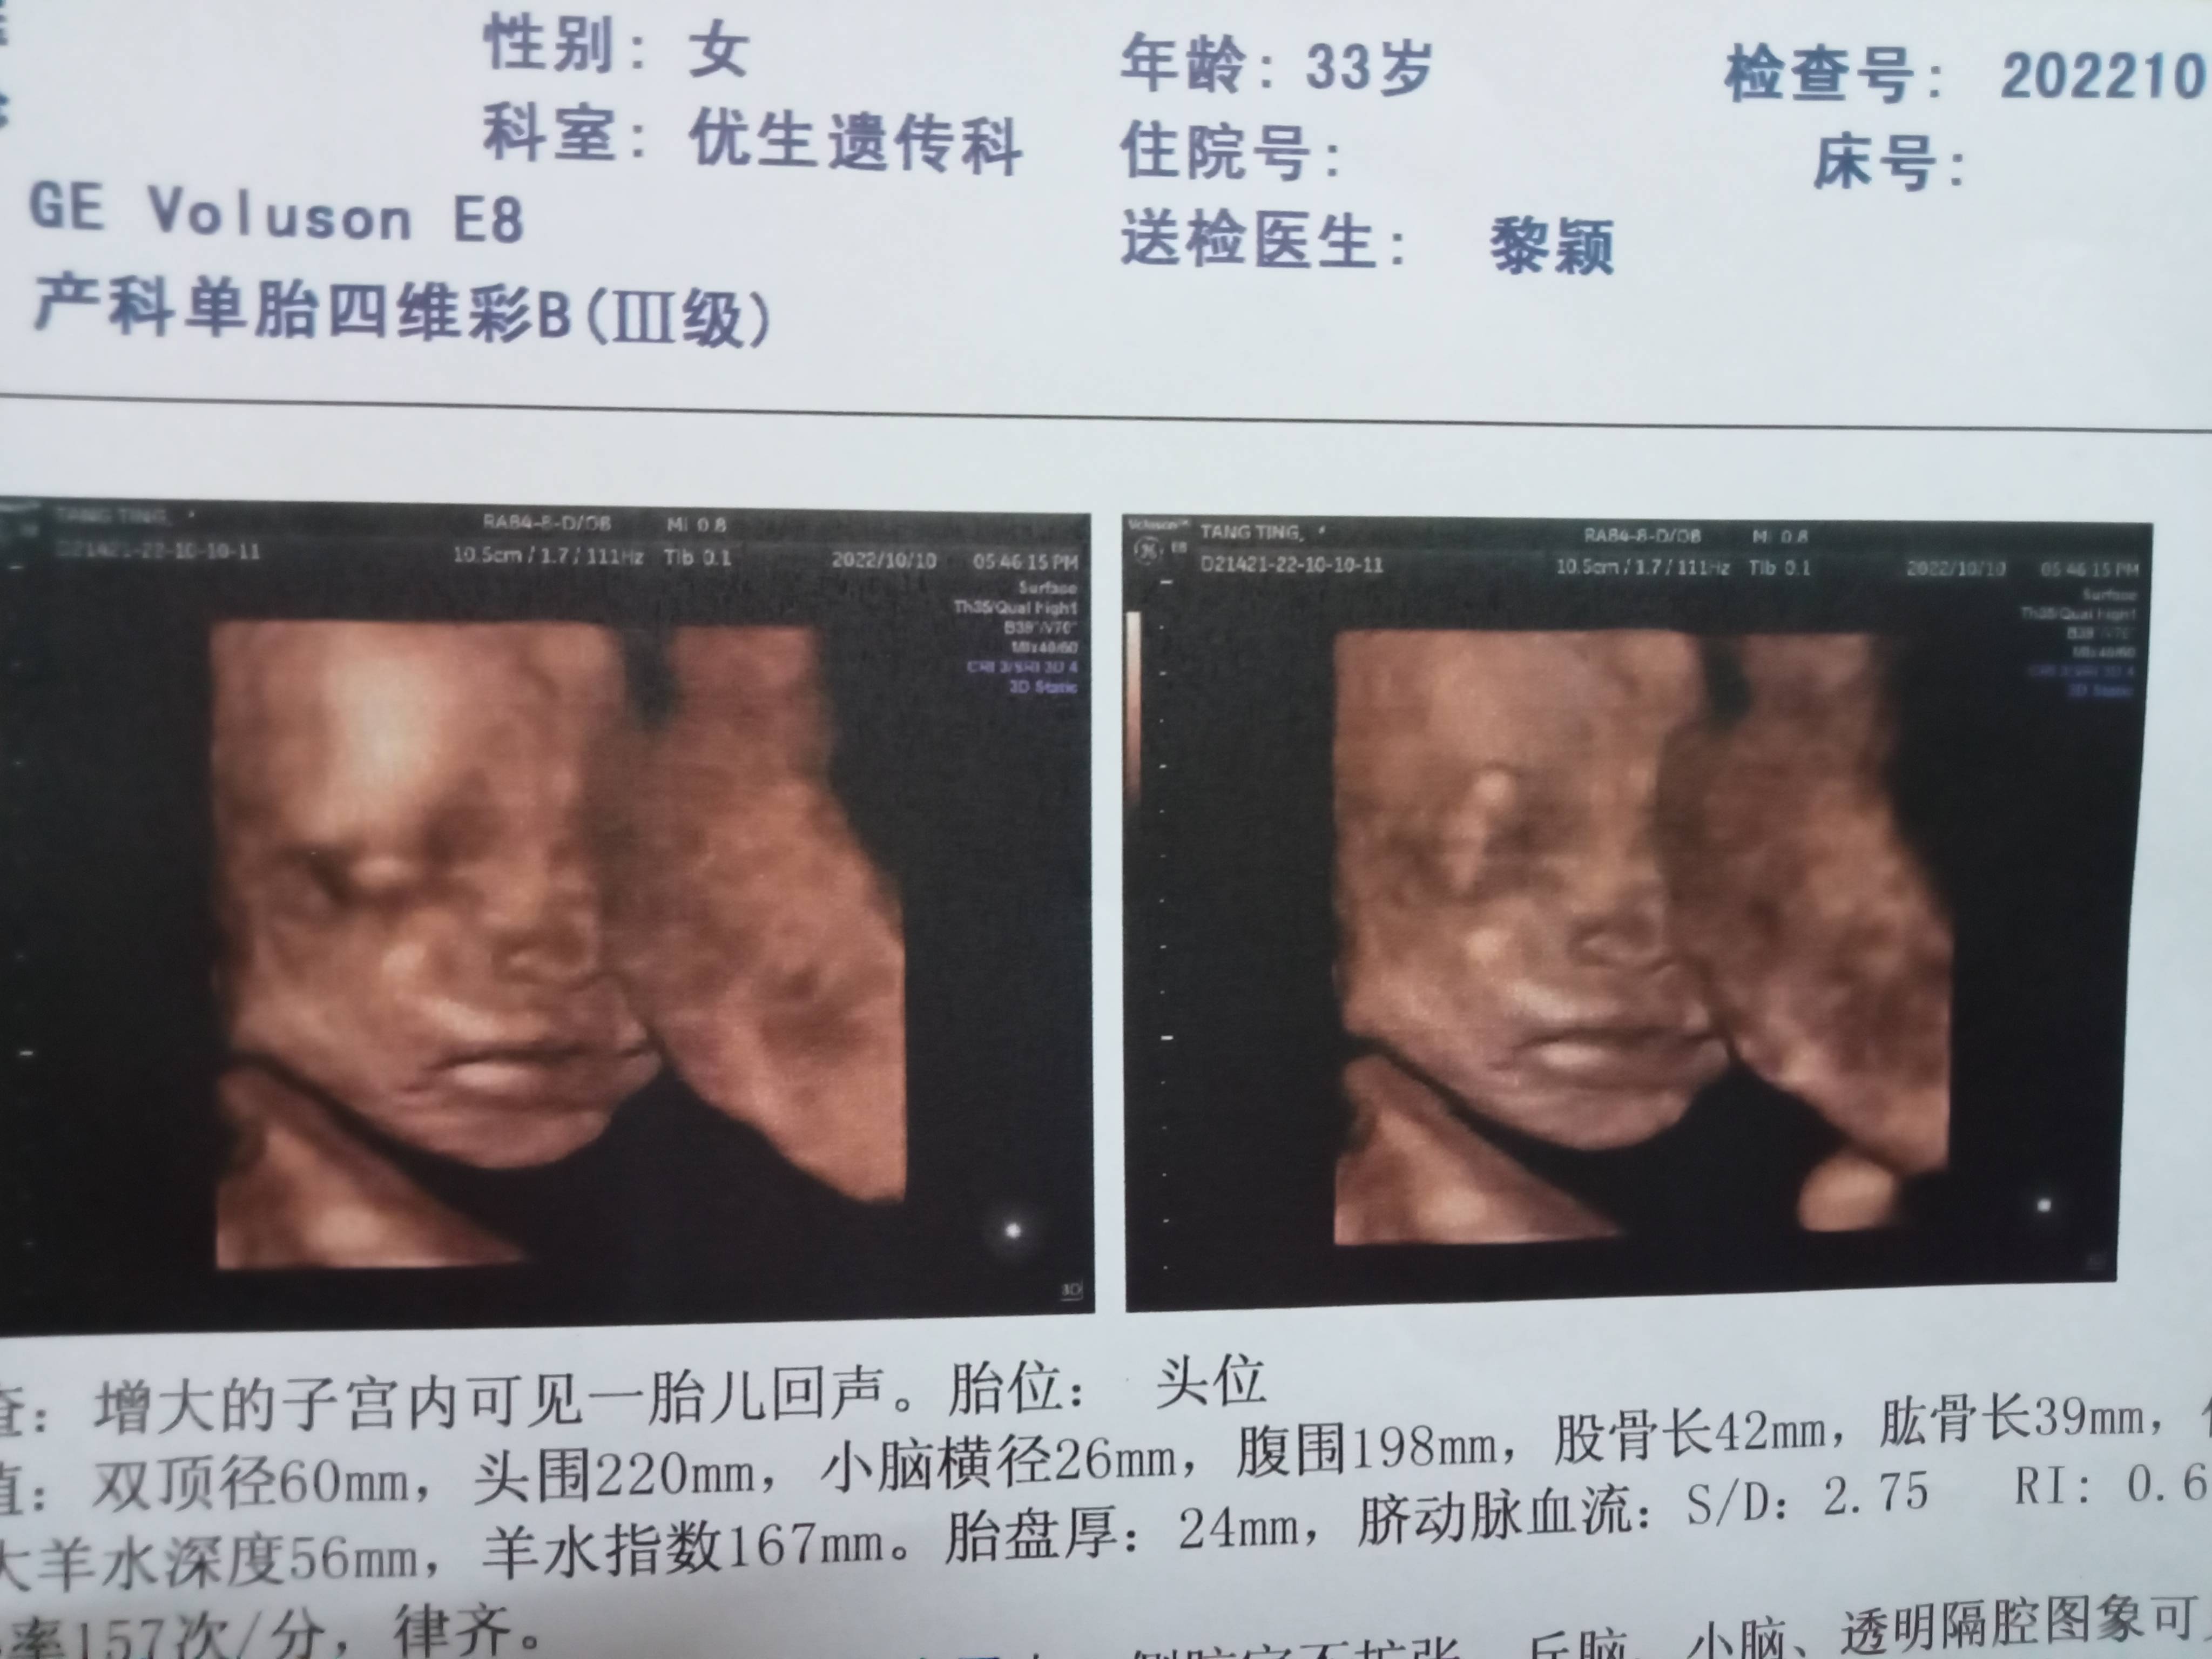

唉,上个月预约四维彩超,这个月10号下午3点,3点40分到我,照了20分钟,彩超那个男医生用照胎儿那个,猛着弄了好几下,左侧也不行,宝宝就是趴着,被男医生叫出去,等他叫,再进来,下午就10个孕妇照四维的,三间四维室,十个孕妇就有五个不过关,第二次叫到我4点40分左右,一进去照,男医生说,宝宝那么快就换位置了,照了几分钟,还是不行,还是趴着,又被赶出去,心情有点郁闷了,怀小女儿时,四维就十几分钟就得了,都是一路绿灯,怎么到这胎,总是不顺利,总是有点折腾,第三次5点半进去,终于可以拿报告了,但总觉得男医生要下班,后面有没有趴着,我没问男医生,他也不好说话,三次进去,就问几周,叫什么名字,就这样,唉市妇幼,有些医生态度真的不好,四维彩超报告拿到了,但医生早就下班了,只能明天再找医生看,唉,四维图像不清晰,羊水穿刺报告拿给医生看,说没问题图片图像真的很模糊,不清晰,还没我14年小女儿的四维清晰,我以为科技越来越发达,图像应该比以前的清晰,谁知,唉,市妇幼,专为孕妇和宝宝的医院,应该仪器比较清晰,谁知是模糊,还是我的四维模糊,别人的四维就清晰,唉,应该四维看来,没问题吧